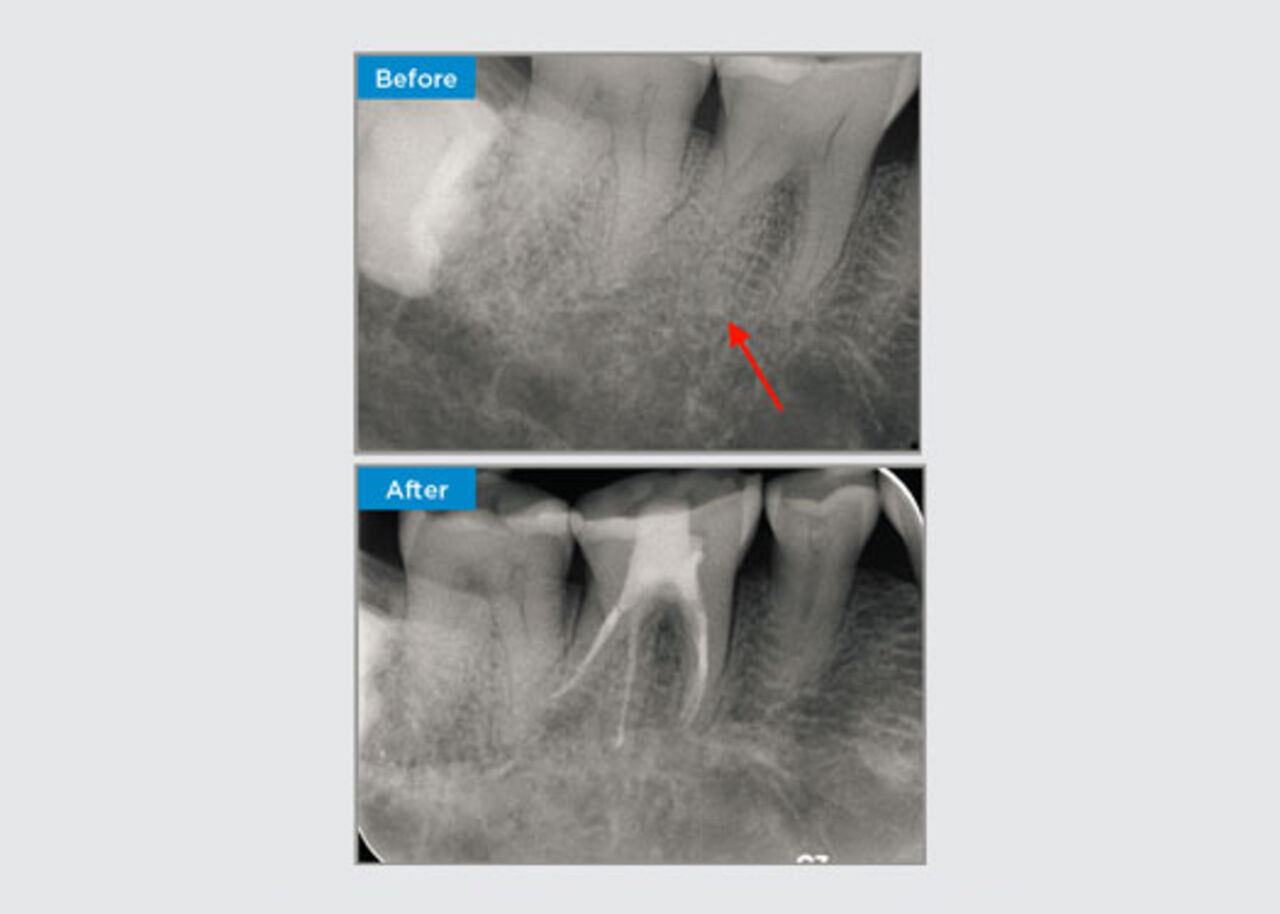

The patient was presented with irreversible pulpitis on tooth 46. From the pre-op radiograph, tooth 46 is presented with an additional distal root (Radix Entromolaris tooth morphology). A CBCT scan has confirmed the presence of DL root with severe root curvature. A careful file selection is critical for this delicate DB root.

Dr Jack Lin, Endodontist, Sydney, NSW Australia